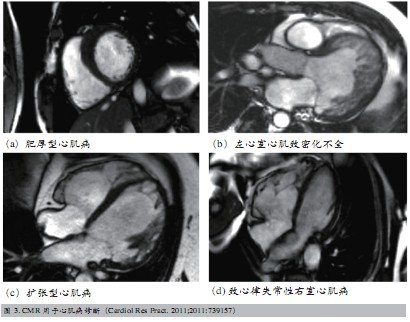

CMR的高分辨力特性可以确定心室腔的大小和结构,动态观察心室形状和容积、室壁运动和心室收缩功能、组织构成及灌注情况,有助于多种心肌病的诊断,对治疗效果及预后判断均有重要价值(图3)。CMR在Tako-tsubo心肌病和缺血性心脏病鉴别方面也有其优势。Tako-tsubo心肌病患者磁共振检查可见心尖区水肿伴收缩功能减低,水肿区无血管,并且无首过灌注缺损和延迟增强等表现。心肌梗死患者磁共振除表现为首过灌注缺损和延迟增强,还有左心室透壁性水肿,水肿区有血管分布。